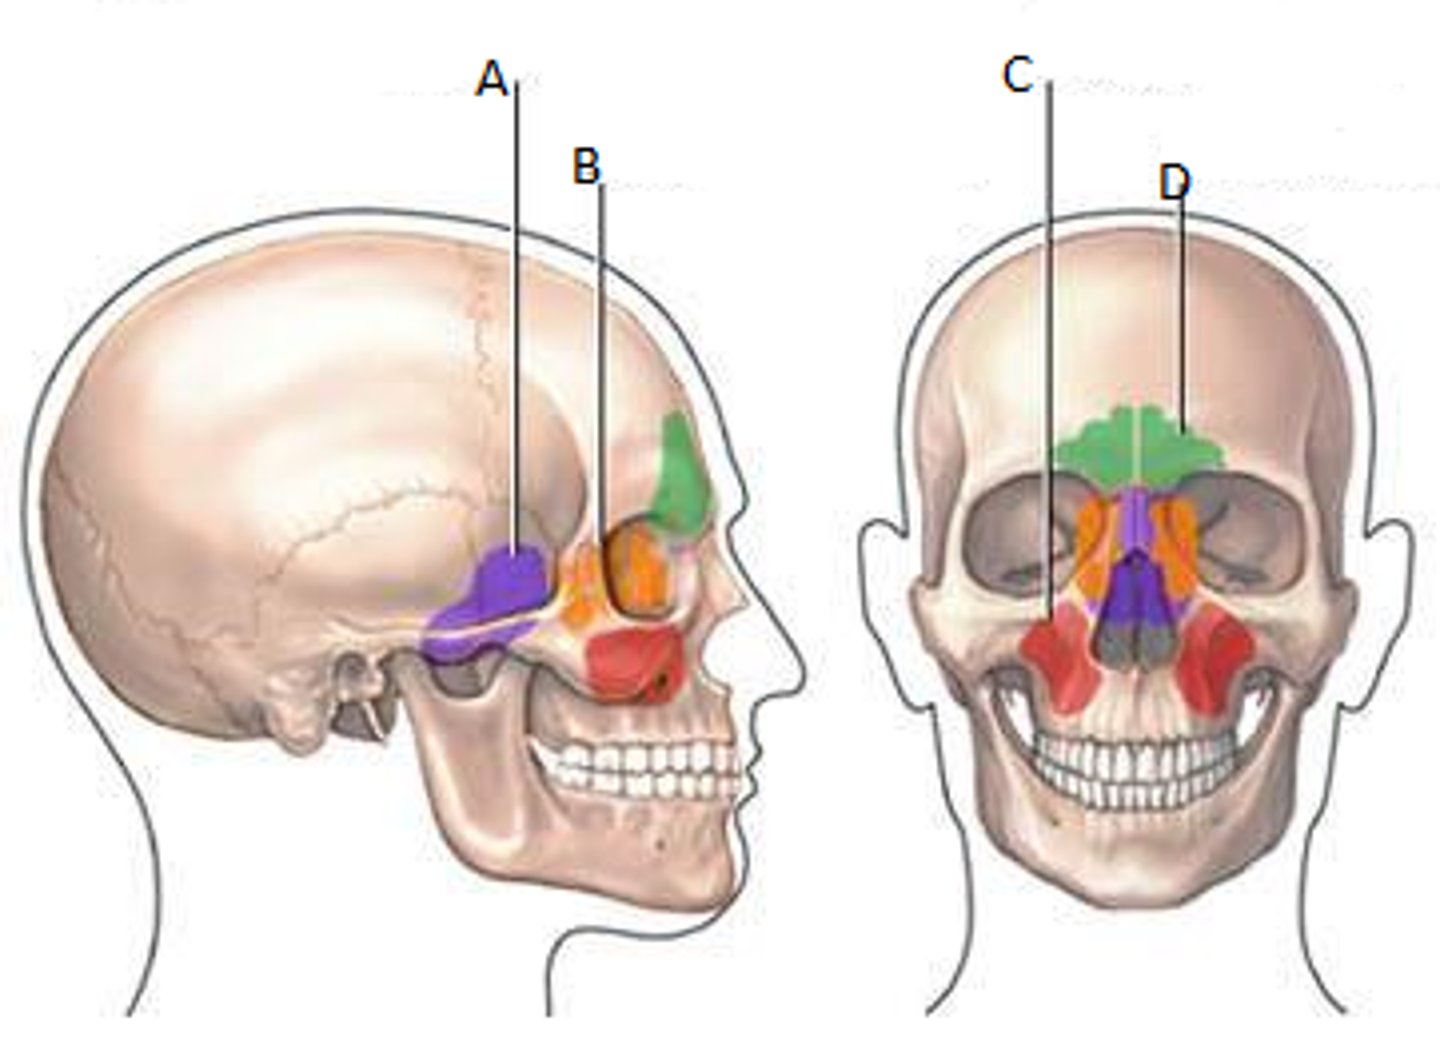

Frontal sinuses

Green

Sphenoid sinuses

Orange

Ethmoid sinuses

Purple

Maxillary sinuses

Red